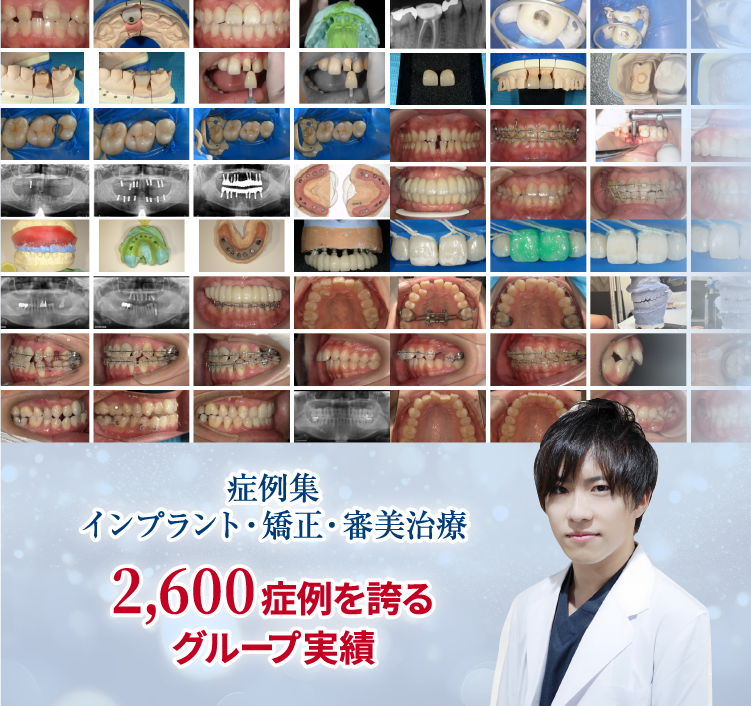

セラミック治療

28歳 女性

前歯のプラスチックが何度も欠けて変色して汚くなっている。

治療経過中の写真

主訴

前歯のプラスチックが何度も欠けて変色して汚くなっている。

治療内容

治療本数:4(12,11,21,22)

治療方法:Cr形成→TEC→ジルコニア

治療費

¥640000 (税込704000)※

※費用は、当時のキャンペーン適用もしくは提供価格を示します。

治療期間

回数:3回

期間:2週間

リスク・副作用

不適切な歯冠形成による歯肉退縮、知覚過敏、歯髄炎、失活による歯の変色等

No.2929